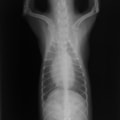

症例:【マルチーズ 12歳齢 去勢オス】

D:胸部レントゲン写真 正面像

E:胸部レントゲン写真 側面像

左側胸壁心尖部領域を最強点とするLevine 5/6の収縮期性心雑音が聴取された。

胸部レントゲン検査において重度の心拡大と肺水腫が認められた。超音波検査では、重度の僧帽弁閉鎖不全症、三尖弁閉鎖不全症、中程度の大動脈弁閉鎖不全症を合併していることが判明した。三尖弁逆流速度から肺高血圧症が示唆された。

ACE阻害薬、ピモベンダン、硝酸イソソルビド徐放剤、ベラプロストナトリウム、利尿剤としてフロセミドとスピロノラクトンを用いて治療を行った。